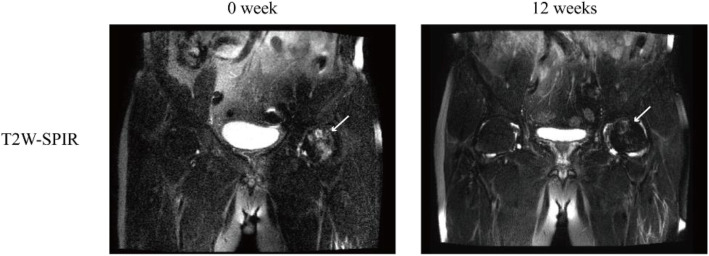

After 12 cycles of focused ESWT treatment, BMES improved significantly, and the area of bone marrow edema decreased significantly (Fig. 4). The patients’ pain significantly reduced, and the joint function significantly improved (Table 2).

Fig. 4.

Cases of bone marrow edema syndrome affecting the femoral head after extracorporeal shockwave therapy